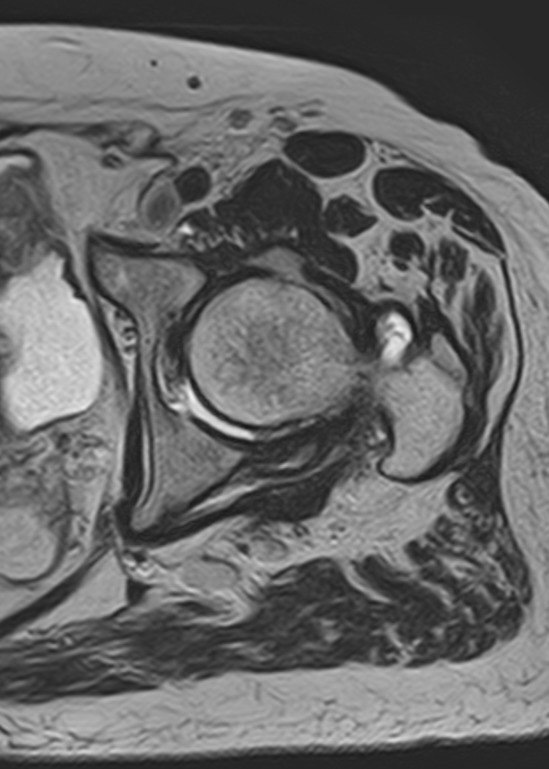

Магнитно-резонансная томография (МРТ) – это высокоточный метод диагностики, который позволяет получить детальные изображения костных и мягкотканевых структур без использования рентгеновского излучения. Расширенное МРТ тазобедренного сустава — это углубленный вариант исследования, включающий специальные протоколы, повышающие точность диагностики.

• Высокое разрешение изображений для оценки мельчайших повреждений

• Специальные режимы сканирования, включая 3D-реконструкцию